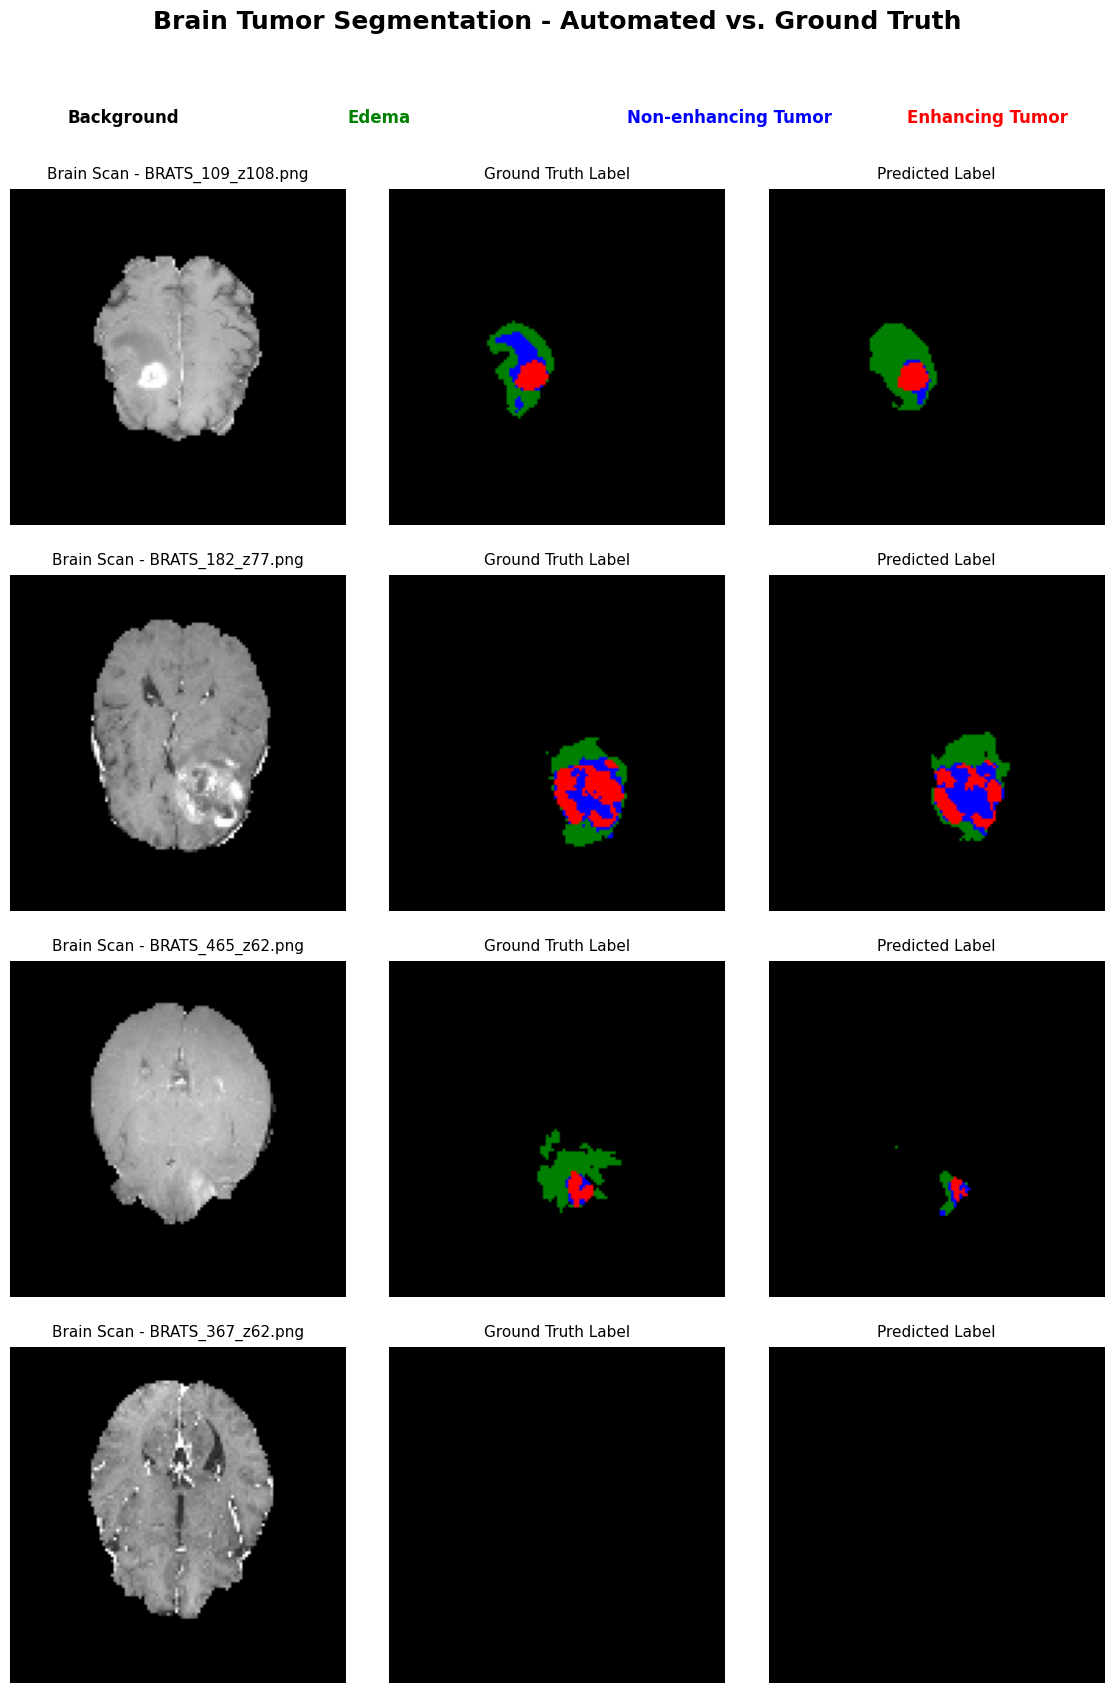

Developed and trained a CNN following the U-Net architecture implemented in Python using PyTorch. It performs image segmentation for identification of edema, non-enhancing tumors and enhancing tumors.